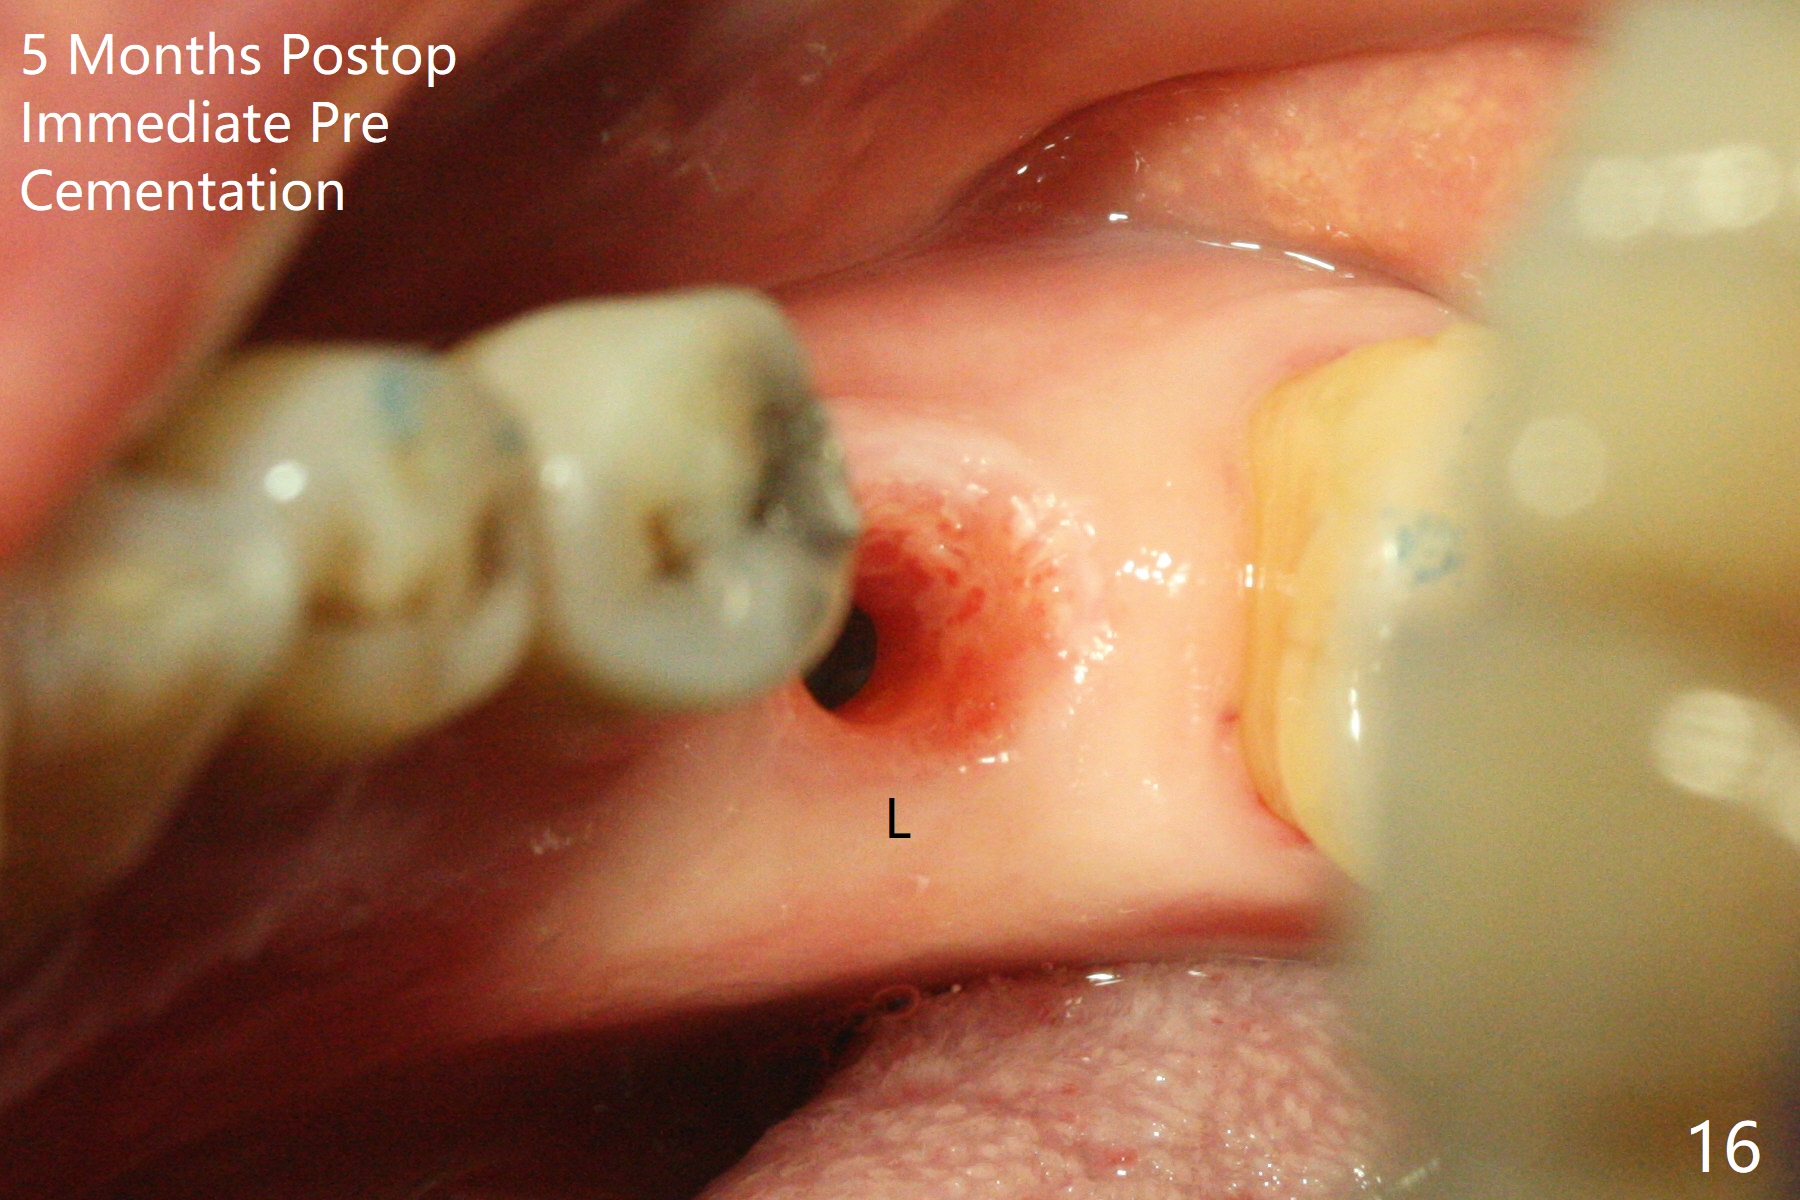

As planned, the crown of the tooth #30 with lingual (Fig.1 L) caries is removed and flattened with surgical handpiece so that the guide is able to be seated without interference. The osteotomy by 10.5 mm offset bone trimmer is lingual (Fig.2 white circle; due to in part the lingual caries and in part design error); in order to let the osteotomy to bounce back buccal, the part of the buccal roots are removed by surgical bur (arrows). The initial osteotomy by 2.2 mm drill is in the middle of the septum (Fig.3). After the last drill (3.5x11.5), the remaining roots are easily removed with proximators; a 4x11 mm dummy implant is placed with low stability and supracrestal lingual (Fig.4). Therefore a 4.5x9 mm final implant is placed with low torque. Following 4x11.5 mm drill, the torque increases to 20 Ncm. With insertion of healing screw, sticky bone (Fig.4 *: .5-1 mm cortical/cancellous allograft) is heavily packed around the implant (arrow), which apparently allows removal of the healing screw and placement of a 6x5.7(3) mm pair abutment without loosening the underlying implant. More bone graft is placed (Fig.6), followed by 2 pieces of PRF membranes. Although the implant is slightly buccally placed (Fig.7, due to over-removal of the buccal root, Fig.2 arrows), it is placed in the septum (Fig.8 S). To further compensate for the low implant stability, setting acrylic is applied in the edentulous area, particularly into the undercuts of the neighboring teeth (Fig.9 *) and around the abutment. The lingual margin of the acrylic dressing is extended (Fig.10 arrow) to cover the soft tissue defect associated with the lingual caries. As compared to the design (4x10 mm, Fig.11), the implant (4.5x9 mm, Fig.12) is placed buccal and ~ 2 mm deeper, reducing the chance of periimplantitis. The acrylic dressing is in place, but has mobility. The gingiva is healthy 2 weeks postop. The dressing is removed 1 month postop; the socket heals around the abutment buccal (Fig.13) and lingual (Fig.14). In spite of the immediate provisional, the abutment margin is substantially subgingival mesial 4 months postop, extremely difficult to take impression. A smaller diameter and longer cuff abutment is placed (Fig.15). The lingual gingiva heals normal 5 months postop, immediately before cementation (Fig.16).